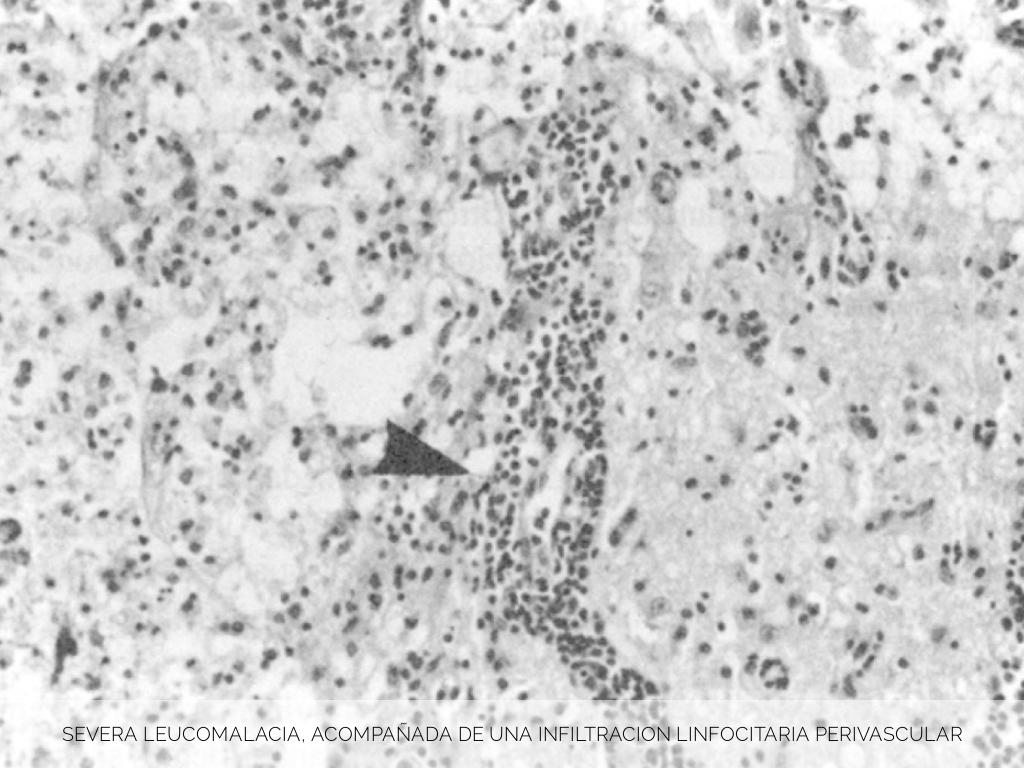

SEVERA LEUCOMALACIA, ACOMPAÑADA DE UNA INFILTRACION LINFOCITARIA PERIVASCULAR